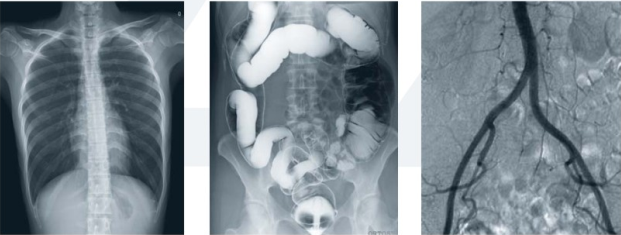

其次,動態dr集常規拍片、胃腸、透視、造影于一體,真正意義上實現臨床病灶的快速定位和精細診斷,大幅提高醫院的工作效率。

末了,動態dr采集面積大幅面,影像可視范圍為17inchx17inch大尺寸,并且能在連續動態中全像素點片,極為關鍵的是還可以進行視頻保存,在專家會診過程中可以回放影像檢查視頻,從而達到準確診斷的目的。同時動態dr還具有全身拼接功能,尤其適用于全脊柱和全下肢攝影,輔助脊柱畸形矯形治療、康復檢查,為臨床提供高精度圖像。

接下來為大家介紹的動態dr準確診斷的兩個實例。

(2)消化道陰性異物

消化道陰性異物就是在x射線透視的情況下,無法顯示的異物,這個異物不阻擋x射線,且能夠透視x射線。

一個成人病人,吃了魚骨卡在喉部,病理表現是嗓子痛、出血;通過用動態dr進行消化道吞鋇棉檢查,一口造影劑,一口棉花;如果魚刺比較小,那么在鋇棉經過的時候魚刺就會掛在鋇棉上,順著造影劑流下去從而達到治療的目的;如果魚刺比較大,那么鋇棉就會被掛在魚刺上,停留在魚刺所在位置;這時動態dr就可以進行定位,然后醫生可以通過定位用胃鏡或耳鼻喉鏡將魚刺取出來。這就是動態準確診斷或準確治療的優勢。